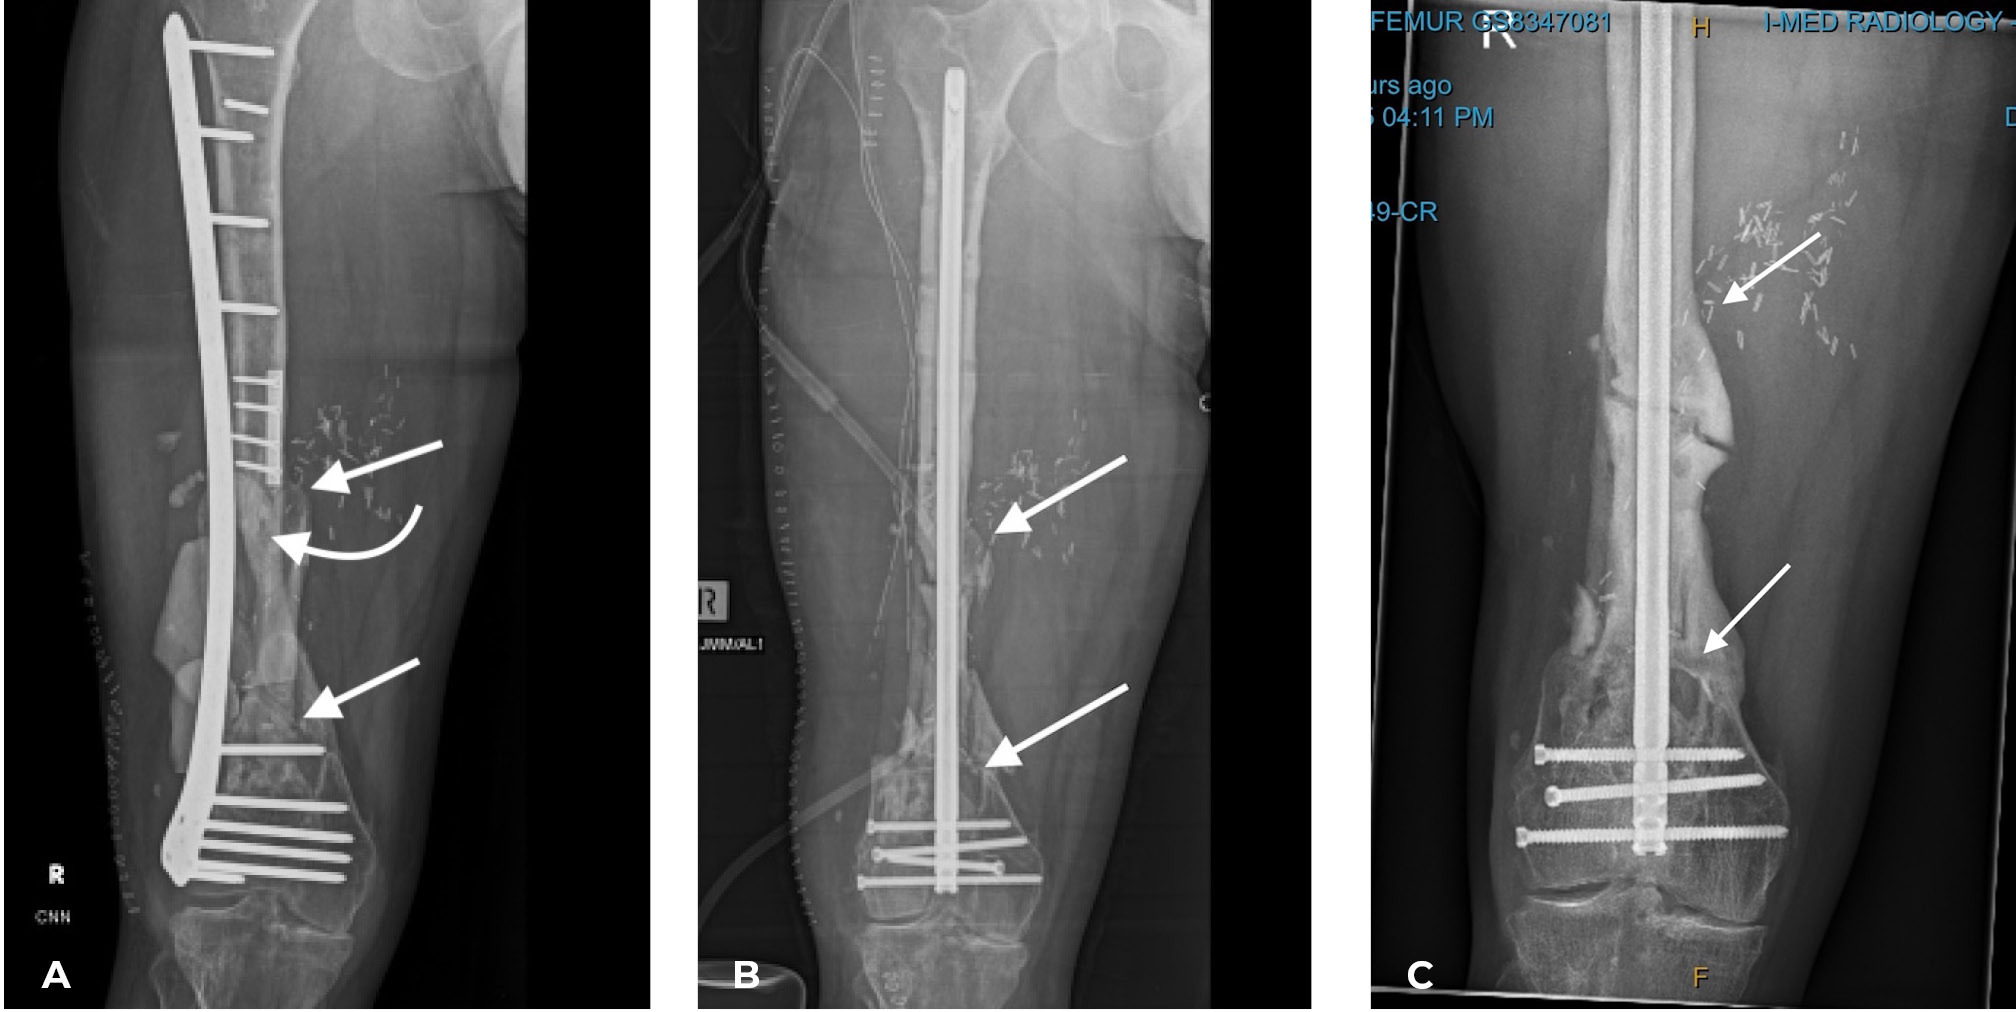

- The lower limb: This is where protected stress on the fibula in the line of weight bearing, is so important, otherwise it will not hypertrophy (see Case 14 below). This is why we always place the fibula within the medullary cavity of the recipient long bone. For the femoral shaft we choose an external fixateur. David Young, an eminent orthopaedic surgeon and a neighbour at the time, designed his fixateur for our first case. Pins are placed above and below the fibula after inserting it into the femur and sited to prevent it ‘telescoping’ within the recipient bone. Three parallel rods are attached to the pins, shown in Case 9, that can be released one at a time to allow stress on the transplant (Figure 30).

The same applies in the tibia, where the fibula is placed always within the medullary cavity of the bone. There it has been maintained again with the external fixateur or simply an above-knee plaster cast. Notably hypertrophy is frequently initiated by an undisplaced, often unidentified stress fracture as shown in Cases 1, 9, 10 and 11 (Figures 5, 30 and 31). If a specific fixateur is unavailable, in an emergency several transverse pins, a bit of bone cement and any nearby long metal rod or stick will do!

The importance of centralising the fibula within the medullary cavity of the femur or tibia is again reinforced by another case done at the Royal Melbourne Hospital. The fibula was used to reconstruct the femur but fixed rigidly with a plate and screws in Case 14 (Figure 34A). Twelve months later there was union but no sign of hypertrophy of the transplant. Then the plate broke. A Kuntscher nail was inserted from above and down through the medullary cavity of the fibula. It shattered forming a row of ‘bangles’ around the nail (Figure 34B). Two years later, having walked on his ‘box of bones skewered by the K-nail,’ he was located and the leg radiographed. Except for one level, there was union and hypertrophy of all bone bangles (Figure 34C).